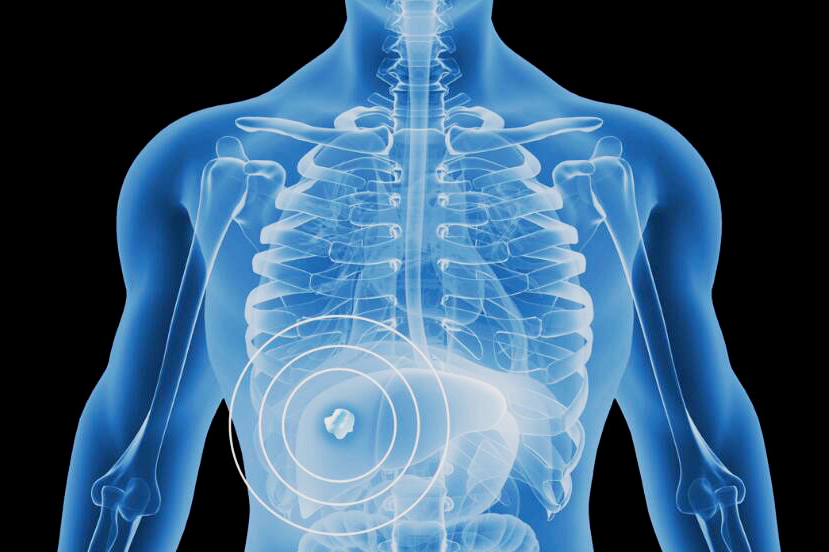

钇90树脂微球它的治疗原理,就是通过一次微创介入手术,把数百万个钇90微球注射至滋养肝脏肿瘤的动脉血管,微球随血液进入肿瘤内部,让钇90释放的β射线近距离杀死肿瘤细胞。

由于β射线平均穿透距离仅为2.5毫米,减少了对正常肝脏组织和毗邻器官损伤,而且肝动脉的血流量高,大部分放射性物质均由肝肿瘤吸收,正常细胞接收极少,这种治疗方式更直接、更精准,而且最大程度避免了传统化疗放疗方式“杀敌一千,自损八百”带来的损伤。

钇90树脂微球被注入患者肝脏血管后,会释放高能量β放射线,可近距离对肿瘤细胞实施精准打击,且对肝脏周围的正常组织没有影响。

△90Y微球治疗过程详解